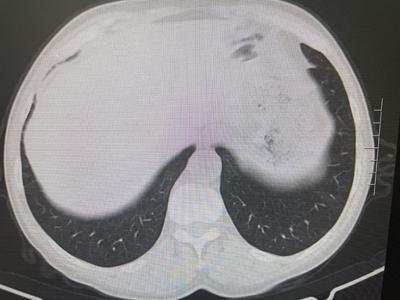

經近2年的門診規(guī)范化診療,病情完全得以控制并處于持續(xù)的穩(wěn)定狀態(tài)。近期復查肺部HRCT示間質性炎癥已完全吸收,肺功能檢測也基本正常,患者皮膚、肌肉、關節(jié)癥狀全部消除,現(xiàn)日常生活已恢復常態(tài),從事以前一樣的勞作。為此,老人及家屬充滿了感激之情。

(2021年12月 肺部HRCT)